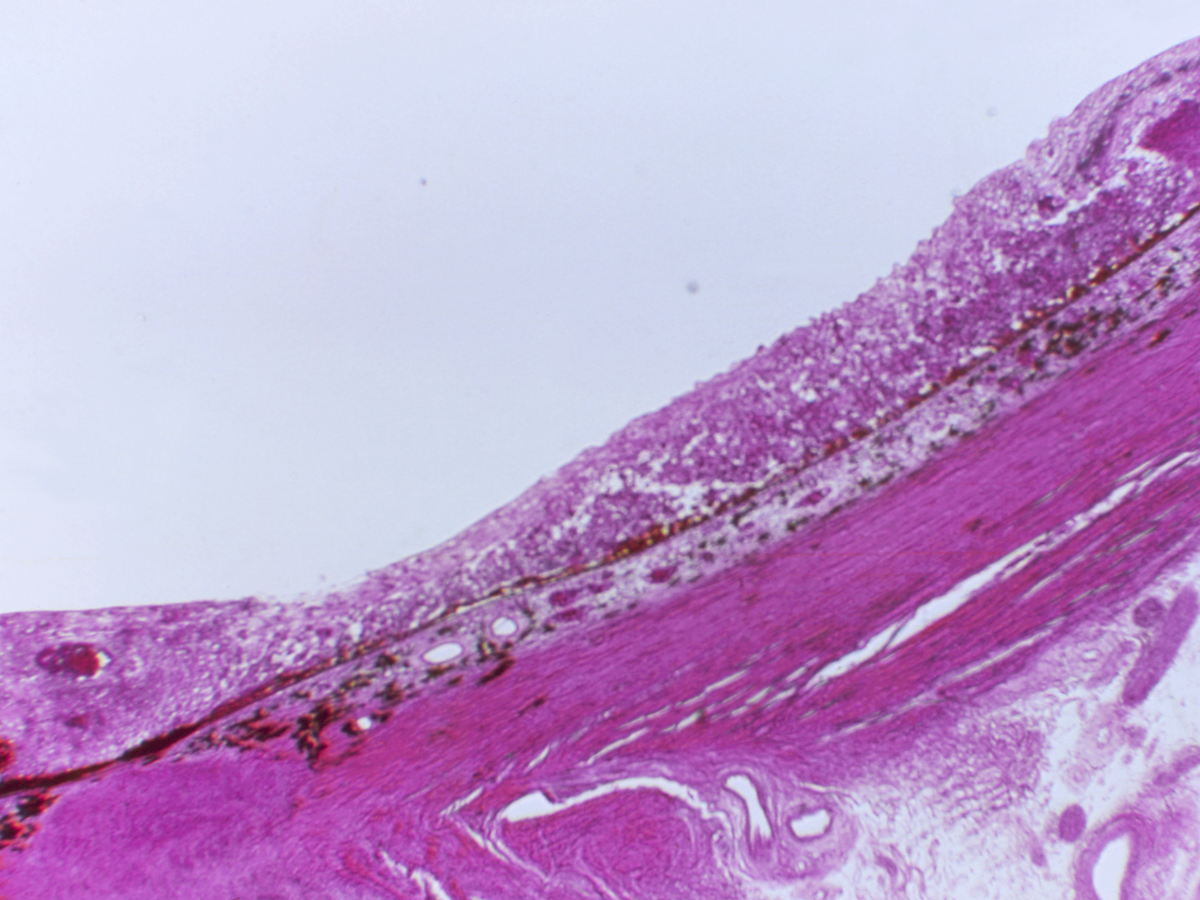

Virchu is the premier histopathology-powered precision oncology platform. Bringing clarity to the complexity of cancer and creating the conditions for world-changing discoveries.

Representing decades of cancer care from world-class institutions, aggregated into a platform designed to deliver insights and power oncology innovation.

dynamic data pipeline

A comprehensive archive of millions of whole-slide images at 40X resolution and growing daily.

Across cancer types including: GYN, GI, GU, Thoracic, Bone & Soft Tissue, Nuero, Renal, Head & Neck, and Breast.